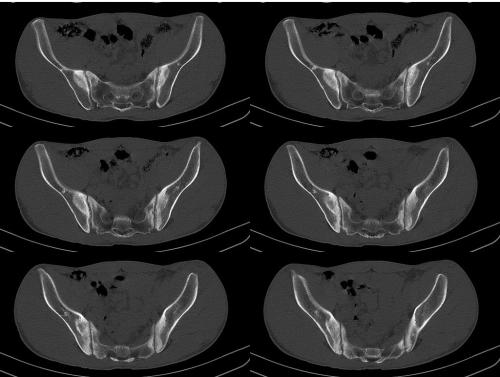

股骨头坏死目前发病率较高,因外伤、大量饮酒、服用激素(如地赛米松、泼尼松、化可的松及甲基泼尼松等)等原因造成股骨头无菌性坏死。强直性脊柱炎的病变可累及髋关节,造成股骨头内纤维组织大量增生,导致关节软骨面受到长期的压力,软骨营养障碍而发生破坏、变薄,较后消失。成都强直性脊柱炎治疗专科医院